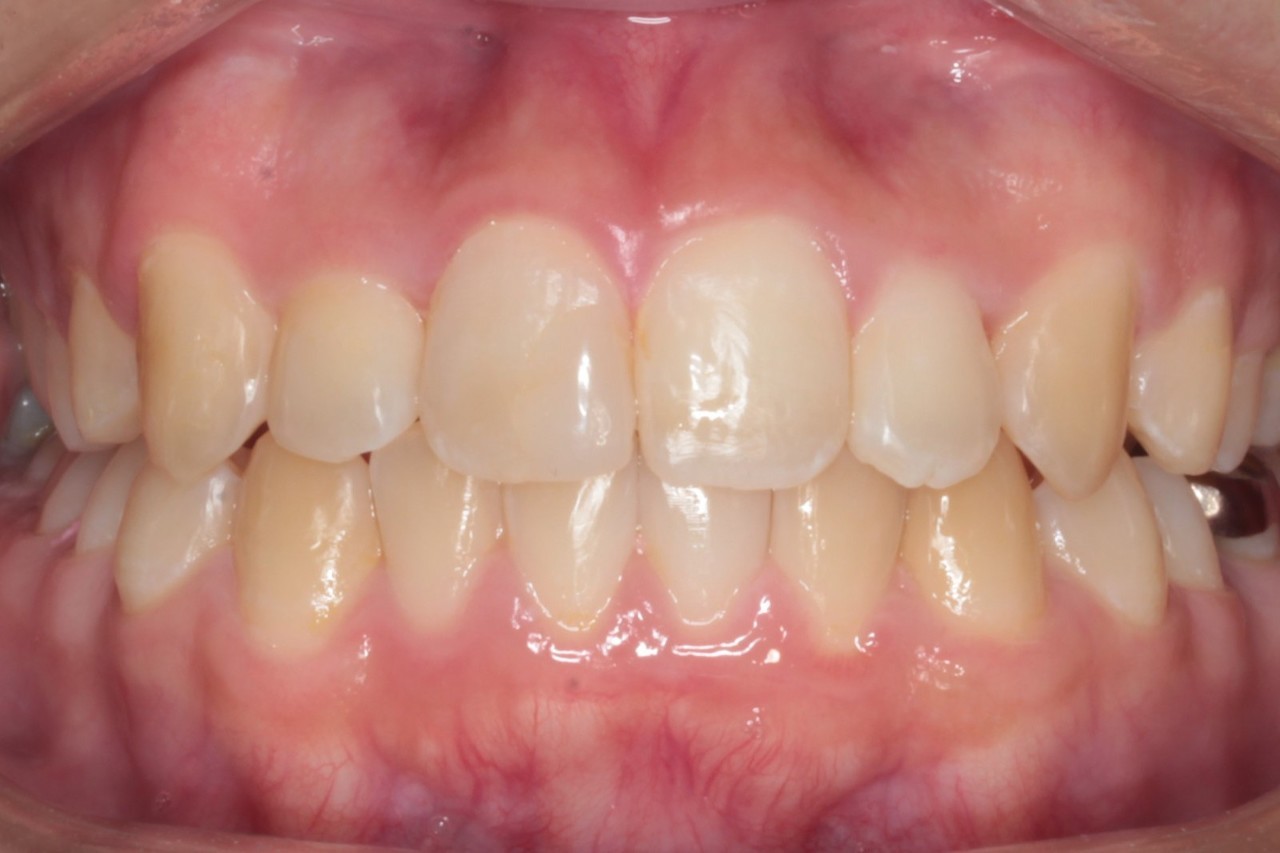

正面 治療前

正面 治療後

調布市の20代男性

主訴:前歯のデコボコを直したい

使用装置:インビザライン

治療期間:約2年

治療費用:93.5万円(税込)

治療結果:叢生が改善されました

今回の症例は写真のように上の中心から2番目の歯が左右とも奥に入り込んでいてかなりスペースのない状態でした